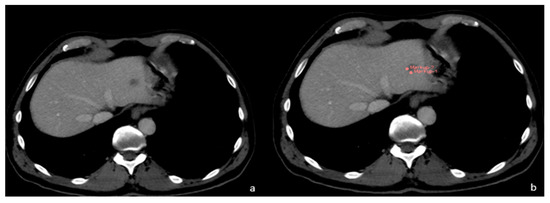

2. Radiomics and Feature Classification

3. Malignant CT Features

3.1. FLL Feature Characteristic